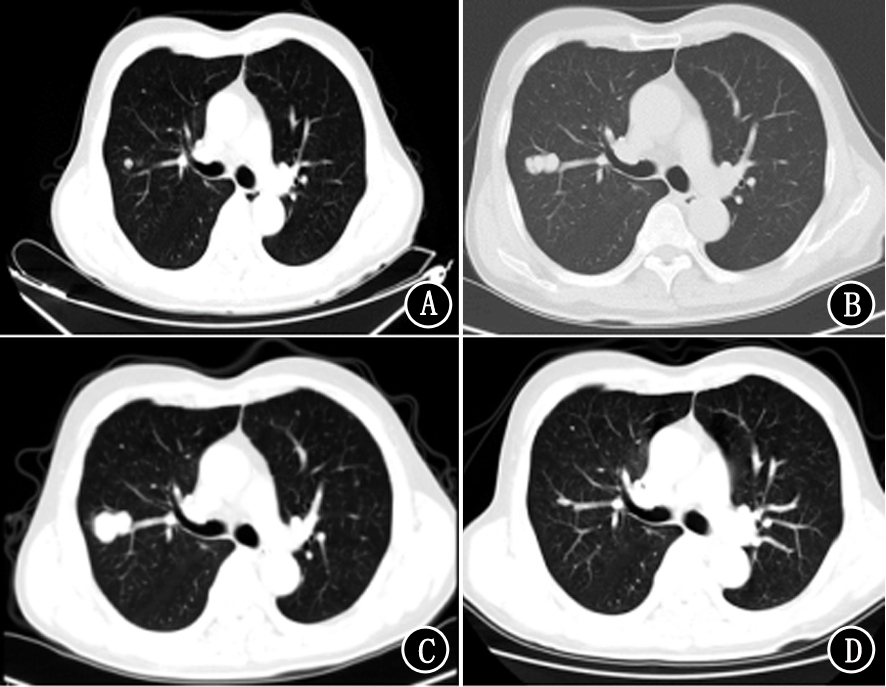

熊敏, 陈翼, 王建波. CT放射组学特征对肺转移瘤的鉴别诊断价值[J]. 国际肿瘤学杂志, 2023, 50(4): 208-213. |